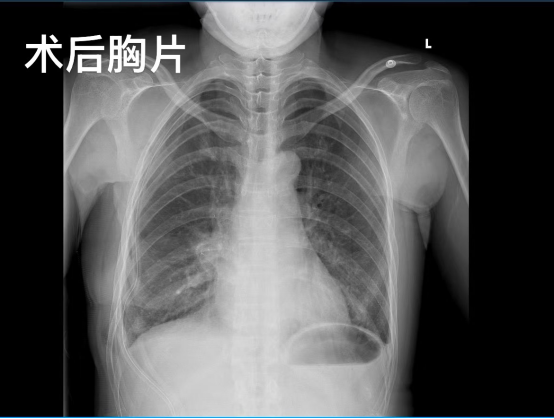

经与李女士进行充分的术前沟通,5月9日,手术进行。在麻醉手术中心团队和护理团队的配合支持下,胸外科团队和乳腺疾病中心团队在乳晕外侧边缘开一个小切口,通过腔镜技术,在3个多小时内,一气呵成完成了“右乳癌保乳”“右乳前哨淋巴结活检”“右肺中叶切除”“叶特异性淋巴结清扫”手术操作。术后,李女士恢复较好,3天后顺利出院,住院时长与普通肺癌患者相同。一个月后复查,李女士仅乳晕处有一个长约8厘米的伤口,伤口恢复良好,乳腺、肺部检查均正常;8月底再次复查,李女士复查结果正常。

(术后一个月复查,李女士与蒲强教授、陈洁教授合影)